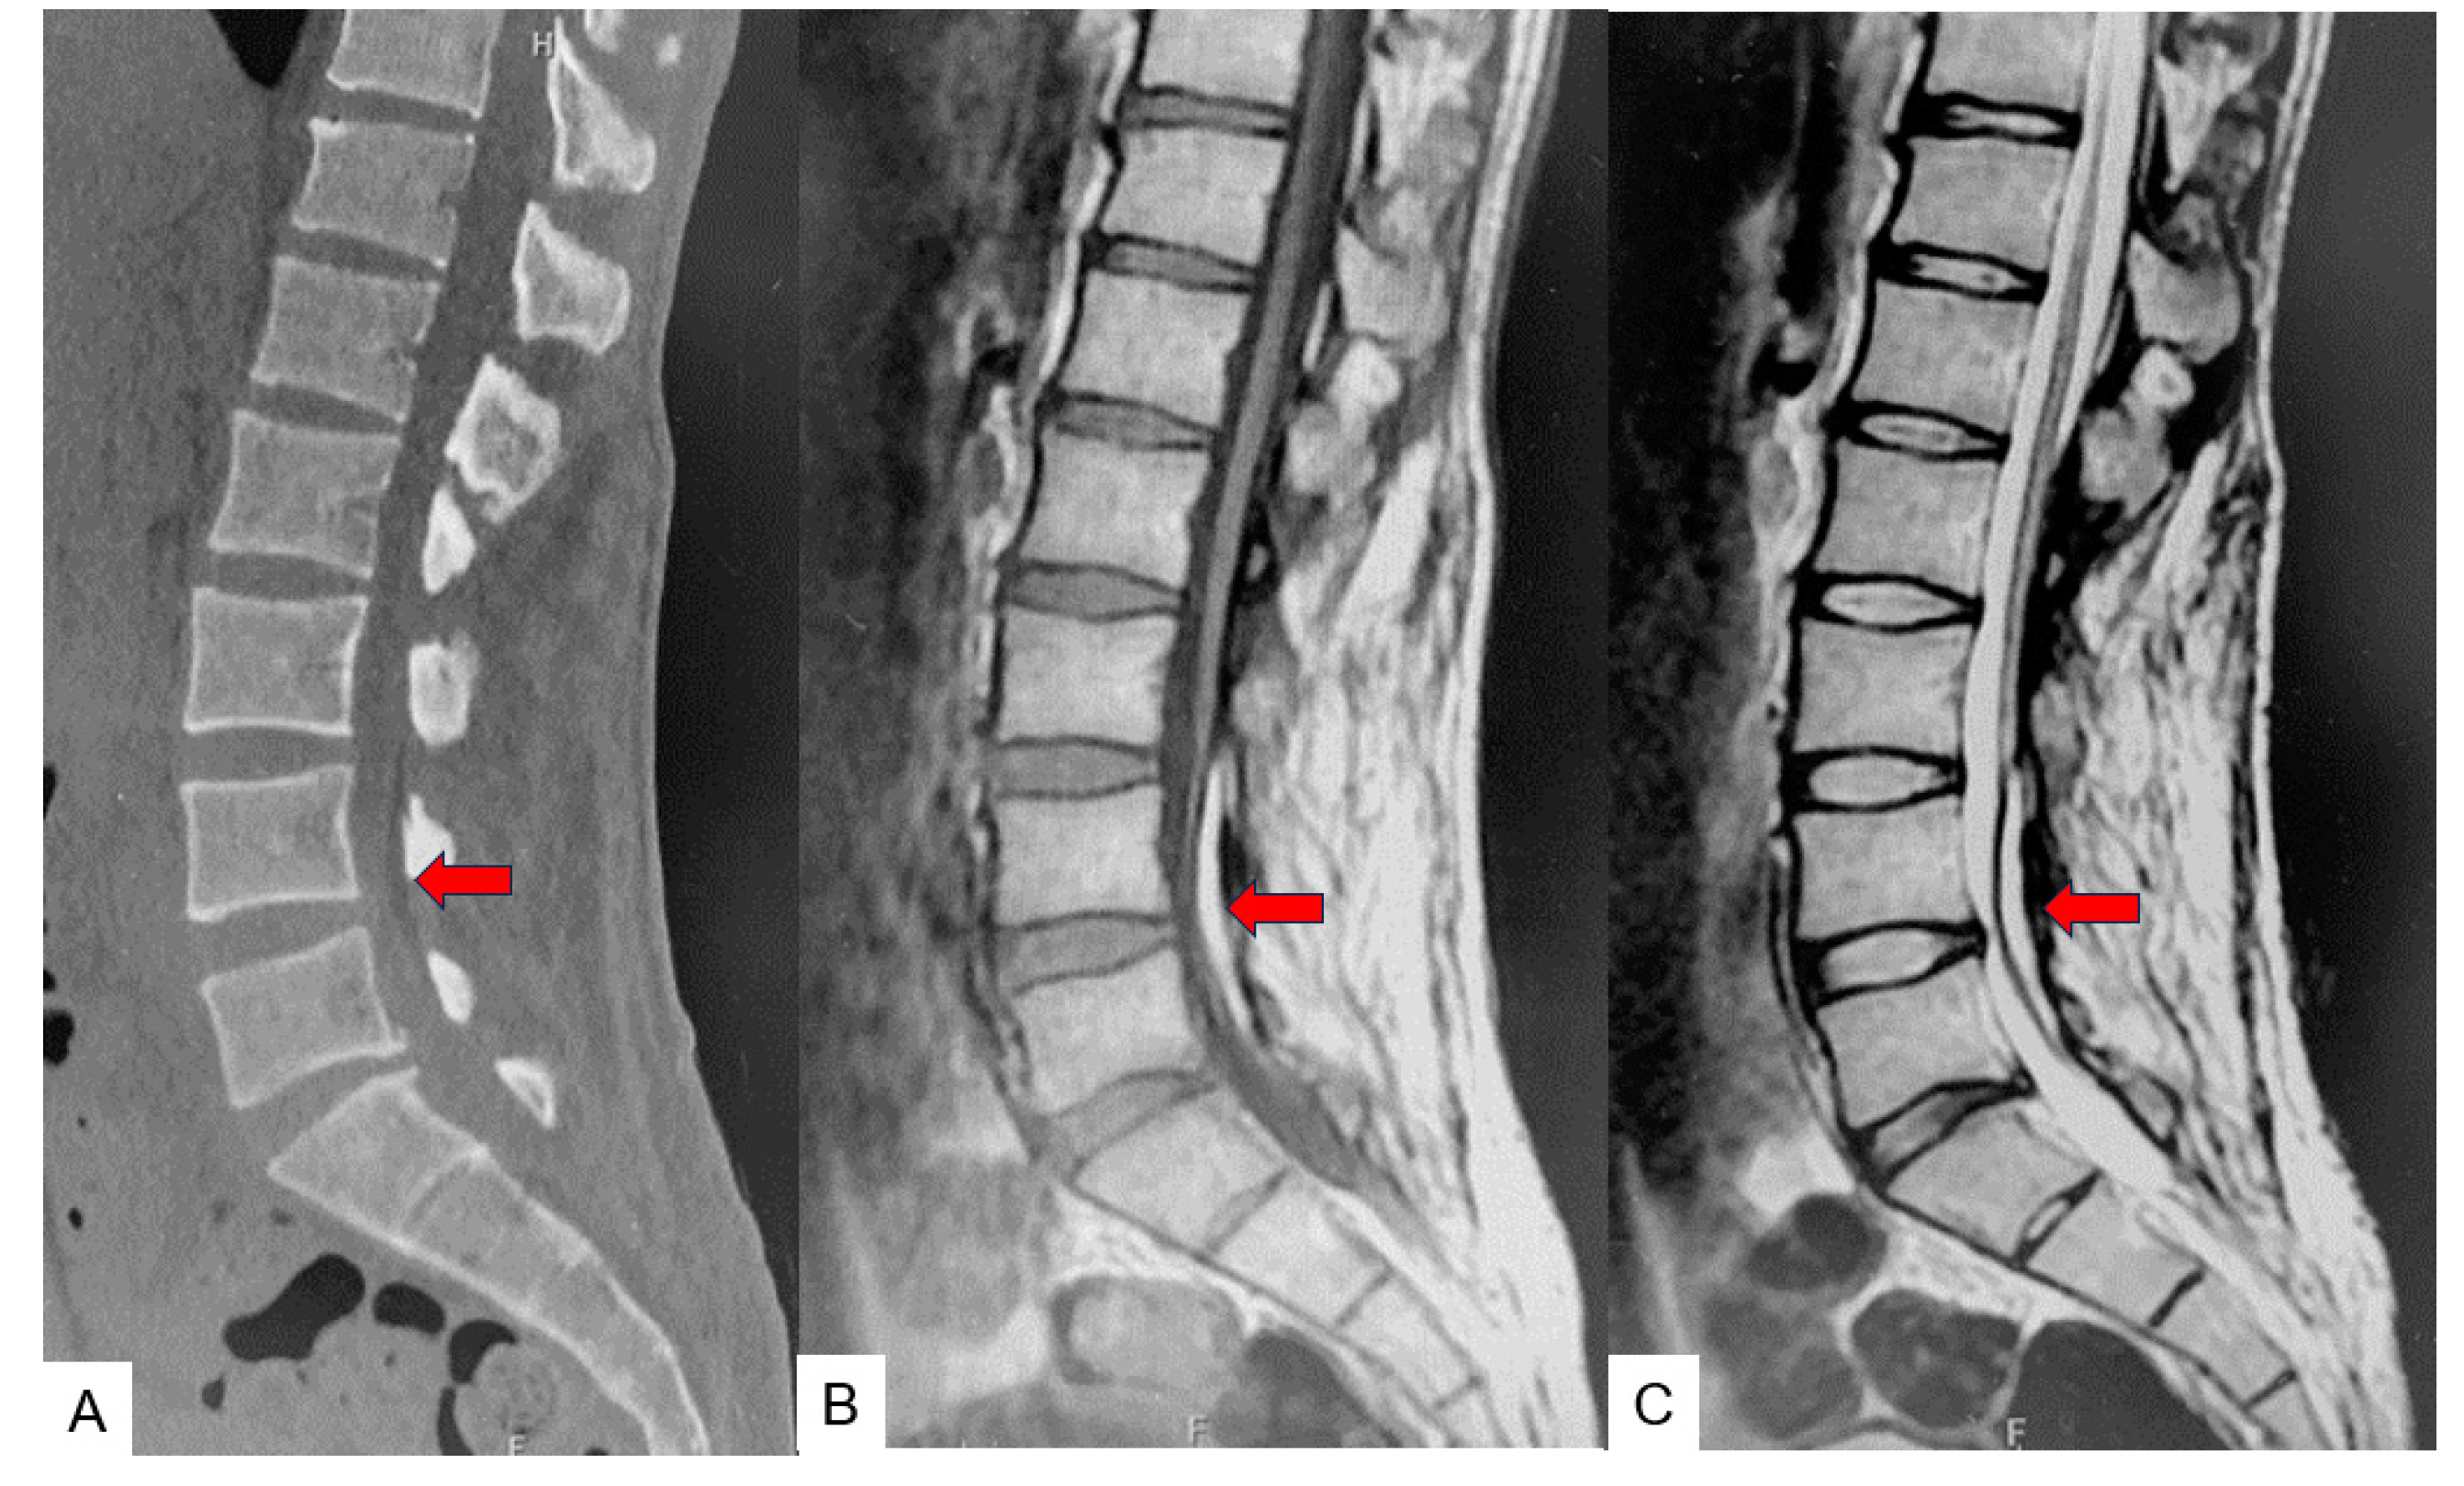

3. Case 2: 33-Year-Old Male, Tethered Cord Syndrome, Conventional Technique

4. Discussion